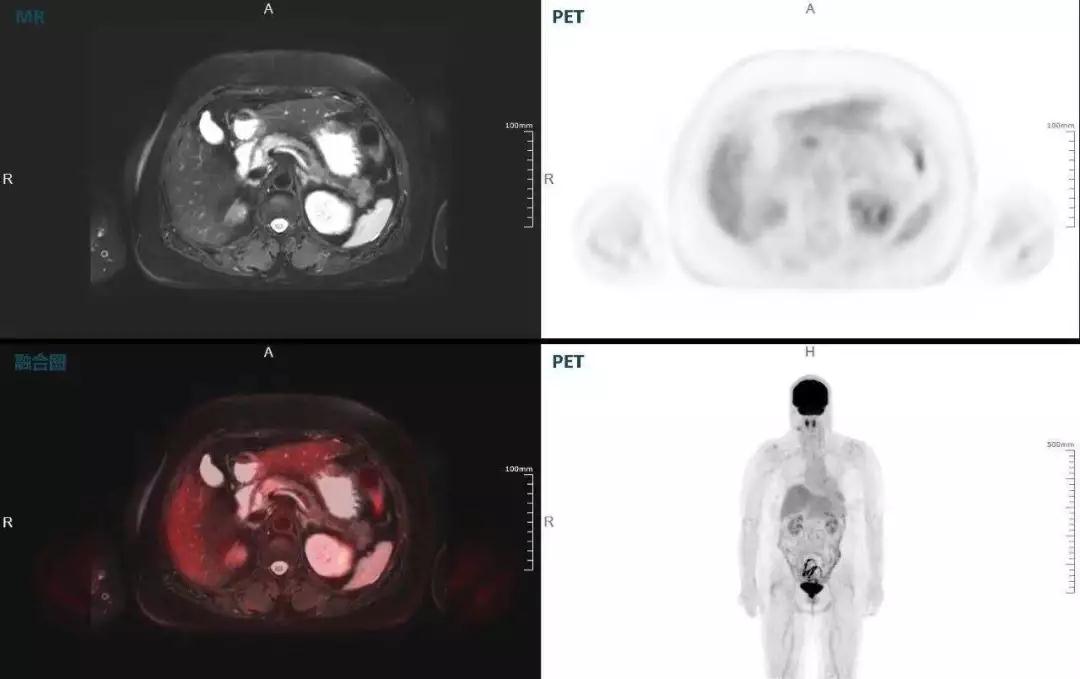

(胰腺腫瘤,MR顯示胰腺體部信號(hào)異常,PET顯示稍高攝取,結(jié)構(gòu)改變和功能異常提示胰腺M(fèi)T可能大。)